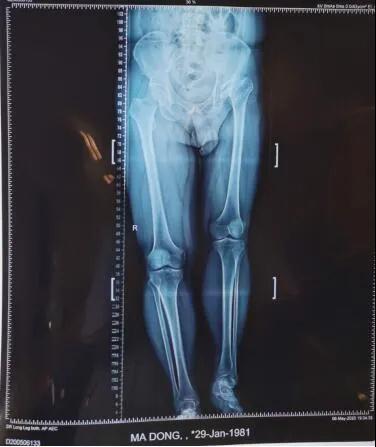

19日,新疆医科大学第六附属医院骨病矫形外科主任李璐兵向记者透露:预计3个月后,有望像正常人一样自如行走。当日,记者在病房走廊看到,马先生手扶助行器,正在练习行走。“17日手术的,今儿就可以下地了。”马先生说。39岁的马先生,年幼时就患有左髋化脓性关节炎,因当时治疗条件有限,造成后期左髋关节骨质破坏严重,左下肢比右下肢短缩了6厘米,走路时跛行很明显,加上左髋关节因为骨质破坏严重导致活动范围受限,就连穿袜子都需要别人帮助。

从拍摄的影像片看出,马先生左侧股骨头已基本消失并且明显上移,错位明显,已与“假”的髋臼形成“假”关节。

整个手术进行了两个小时,将置换后的髋关节假体准确复位,为患者重建了髋关节并且矫正两条腿基本恢复等长。